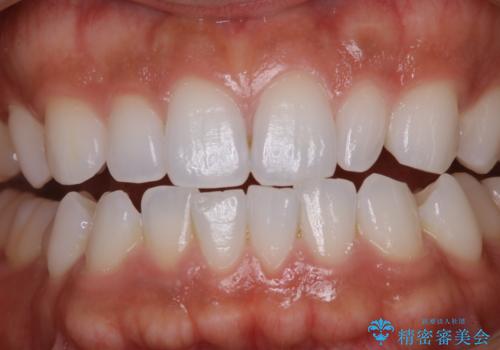

- しばらく歯科でのクリーニングをしていないため、きれいにしたいとのことでした。

PMTC30分コースを行いました。

PMTCは審美的な面だけではなく、虫歯や歯周病予防にもなります。虫歯や歯周病予防のためには、お口の中を清潔に保つことが大切です。